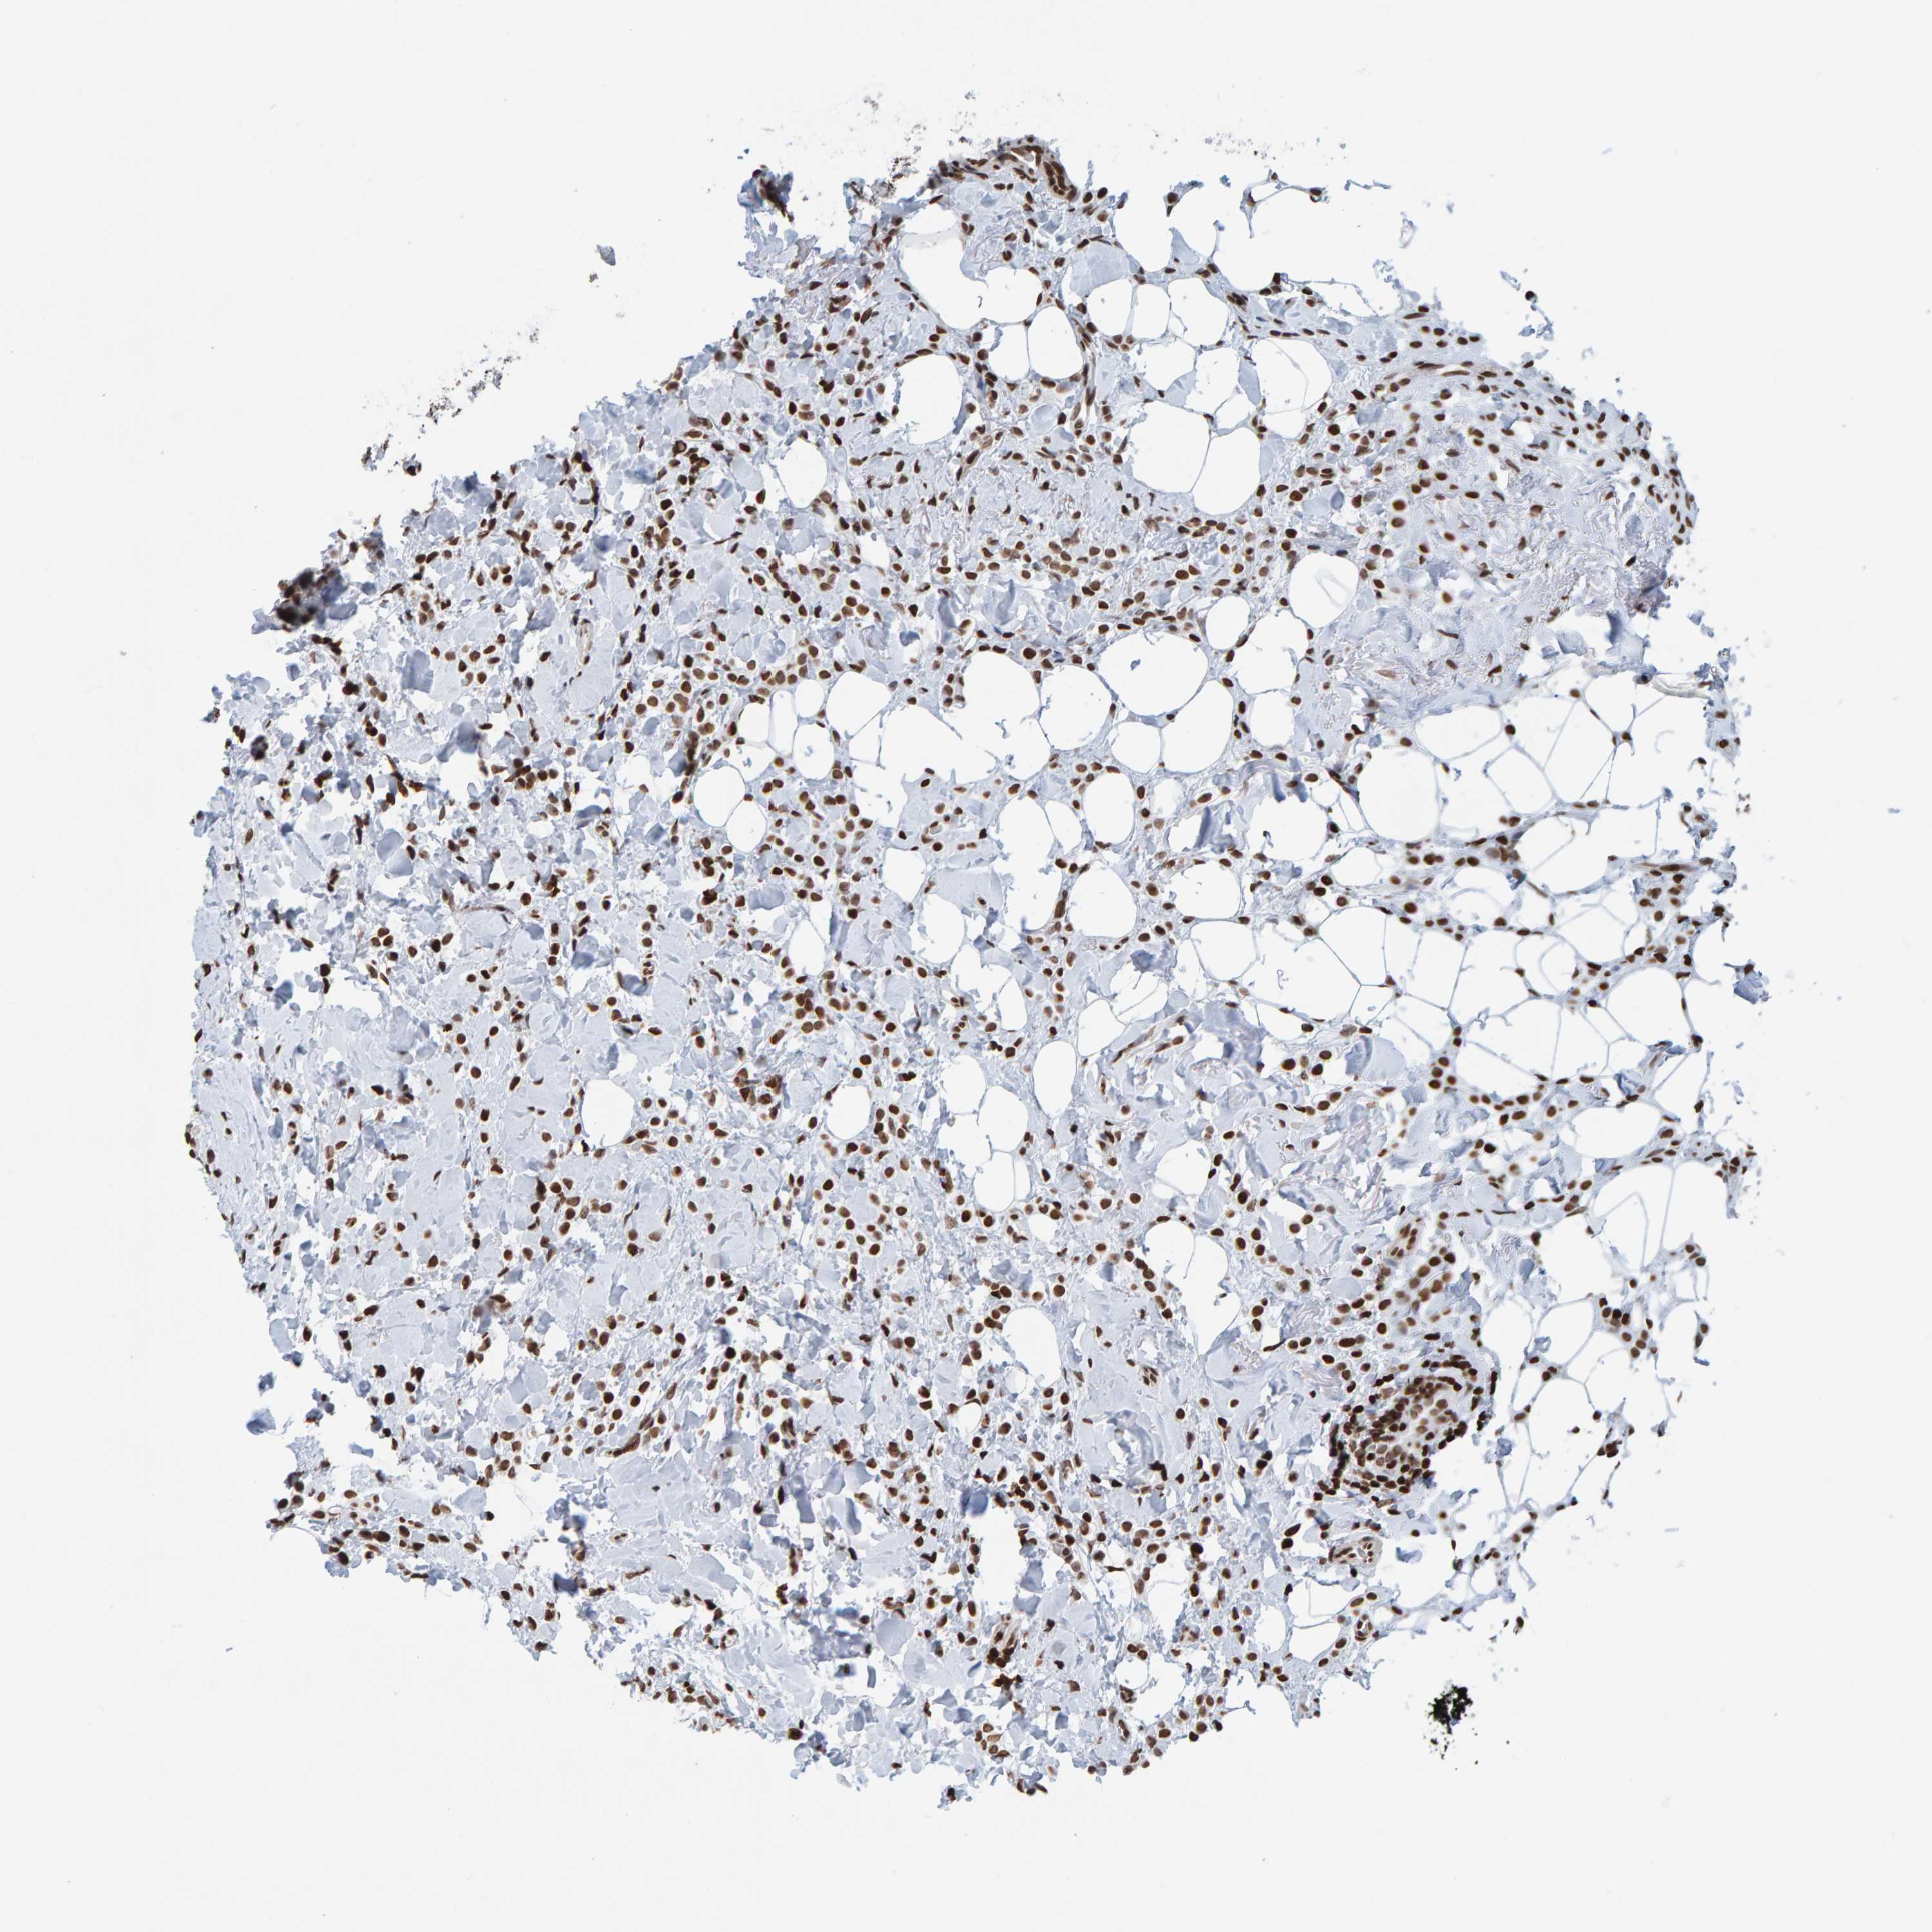

CANCER BREAST CANCER Show tissue menu

BRCA TCGA BRCA VALIDATION PROTEIN EXPRESSION